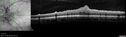

Bullous Retinoschisis - Asymptomatic54 viewsDec 17, 2025

Bullous Retinoschisis - Asymptomatic61 viewsDec 17, 2025

Bullous Retinoschisis - Asymptomatic57 viewsDec 17, 2025